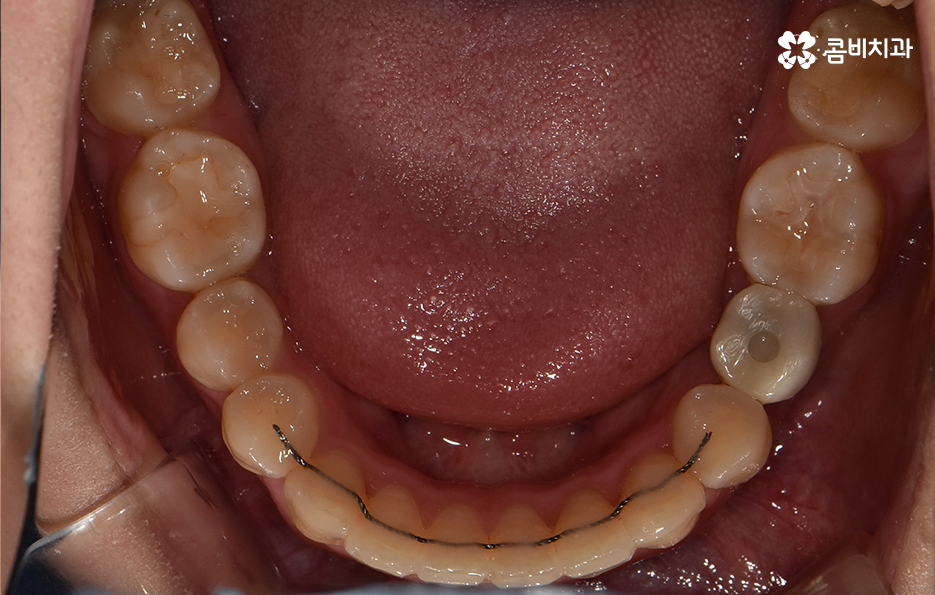

덧니는 윗니와 아랫니에 모두 있거나 앞니에 살짝 있는 수준의 덧니도 있으며 덧니가 심한 경우에는 개방교합으로 인해 입이 잘 다물어지지 않는 경우도 있기 때문에 덧니가 심한 정도에 따라서 치아교정의 계획은 세부적으로 달라질 수 있어요

덧니가 심하지 않은 경우에는 비발치로도 충분히 교정을 하는 경우도 있겠지만 덧니가 심한 경우에는 덧니 발치 교정을 통해서 치료가 진행되는 경우가 많이 있는데요. 그 이유는 치아교정의 원리를 생각하더라도 치아를 재배치하기 위해서는 기존의 치아가 움직일 공간이 필요한데 덧니는 치열이 이미 완성되고 있는 상태에서 치아가 나올 공간이 부족하여 덧니가 되는 경우가 많다는 점에서도 치아의 이동 공간을 확보하기 위한 발치가 필요할 수 있는 거예요

반대로 발치를 하는 것이 치료 결과에 좋지 않거나 덧니가 심하지 않은 경우에는 되도록 비발치로 교정을 진행하는 경우도 있다는 점도 알아두시면 좋을 거예요. 치아교정은 치열만 고려하여 치료 계획을 세우지 않고 결과에 대해 고려하여 계획하는 만큼 치료 뿐 아니라 유지관리까지 오랫동안 믿고 찾을 치과를 선택해야 하며 무엇보다 자신에게 적합한 치료 계획을 잘 세워보시길 바라고 있어요